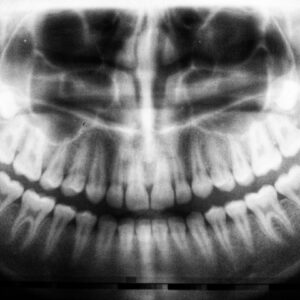

Photo Dental X-ray

Tooth Decay Caries

Tooth decay, commonly referred to as caries, is a progressive condition that affects the hard tissues of your teeth. It occurs when the enamel, the outer protective layer of your…

Tooth Decay Child

Tooth decay, also known as dental caries, is a common yet preventable condition that affects children worldwide. As a parent or caregiver, it’s essential to understand that tooth decay occurs…